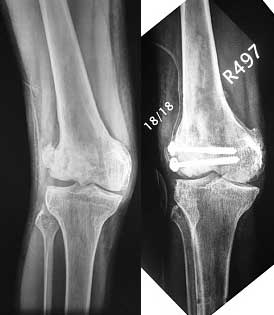

This 20 year old patient sustained a fracture in the lower end of the femur, one and a half years ago, with a compound wound over the fracture area. Notes at that time mention a compound fracture dislocation, with a loss of part of the lateral condyle. This was treated by debridement, and external fixation. After two weeks, the lateral condyle (coronal fracture) was fixed by a screw and k wire in an AP direction.

At present, he has a valgus deformity of the knee, with 0-45 degrees of movt. The knee is stable to examination, could not be corrected to neutral from the existing valgus, and despite the deformity he is walking on it, albeit with pain and some difficulty.

I cannot make certain from the AP whether the screw and KW are still present. The lateral however shows that the lateral condyle was fixed with disregard to the bone defect. So it was proximally displaced in relation to the medial condyle with the resultant valgus. I would do an open wedge osteotomy with bone graft and internal fixation. However, this would require a precise estimate of the correction angle and placement of the fixation device. I would use a DCS.